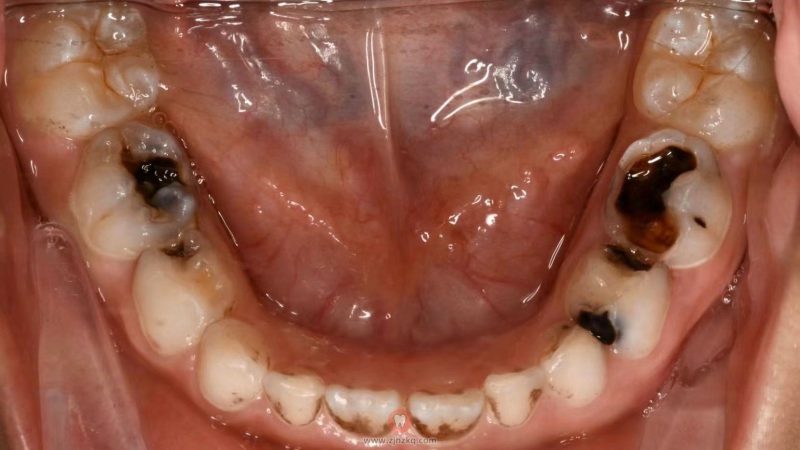

儿童烂牙黑洞图片 杭城看牙记 • 2025年4月10日 09:09 • 看牙科普攻略 儿童烂牙黑洞图片分享大家,当牙菌斑已经渗透到牙齿内部,导致保护层受损,牙体结构遭到破坏,这便是龋齿的形成。 本文内容源自网络仅供参考,不作为诊断医疗依据,更多查询请 → 在线咨询客服